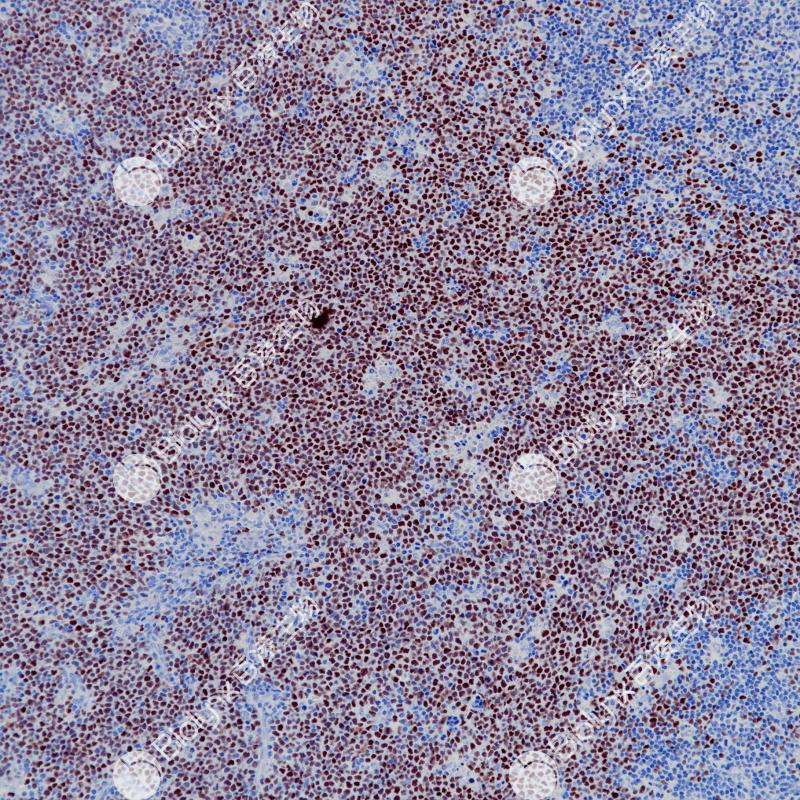

扁桃体Bcl-6(BP6261)染色

Bcl-6是一种编码为kruppel型锌指95kDa的原癌基因蛋白,具有诱导细胞凋亡功能。Bcl-6主要表达在正常生发中心B细胞及相关的淋巴瘤中。研究显示,在非霍奇金氏淋巴瘤中,Bcl-6原癌基因涉及染色体3q27基因重排,在33-45%弥漫性大B细胞淋巴瘤中也检测到Bcl-6基因重排。据报道,免疫组织化学染色在滤泡性淋巴瘤、弥漫性大B细胞淋巴瘤、伯基特淋巴瘤和结节性淋巴细胞为主型的霍奇金氏病中可以检测到Bcl-6基因产物。

阳性对照

弥漫大B细胞淋巴瘤

细胞核